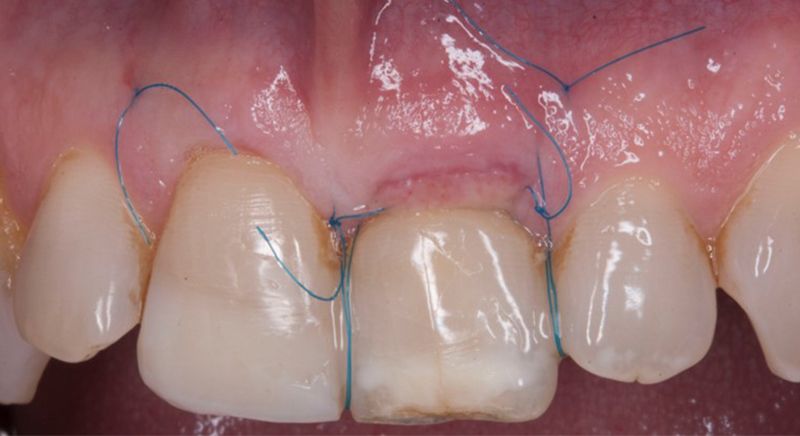

Once the hard and soft tissues had healed, 6 months after the surgery, a good volume remained in the vestibular area. It was then that we could consider an implant, using guided surgery to ensure it was placed in the correct three-dimensional position.

After 6 months of healing, a minimum crestal incision was made to change the 3mm abutment underneath for a 5mm abutment that would be exposed to the oral medium.

Finally, a definitive metal ceramic crown was designed and manufactured for 2.1 and a veneer for 1.1.